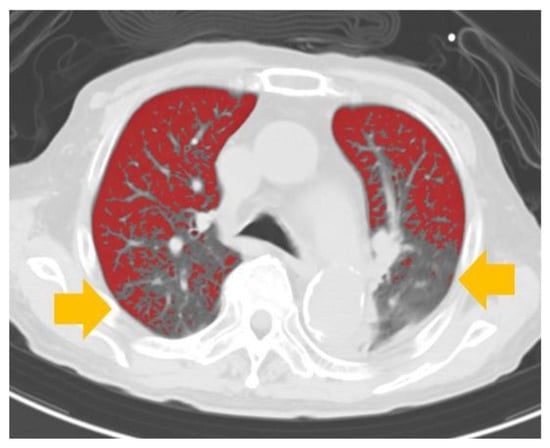

Automated Volume Analysis of the CT Images